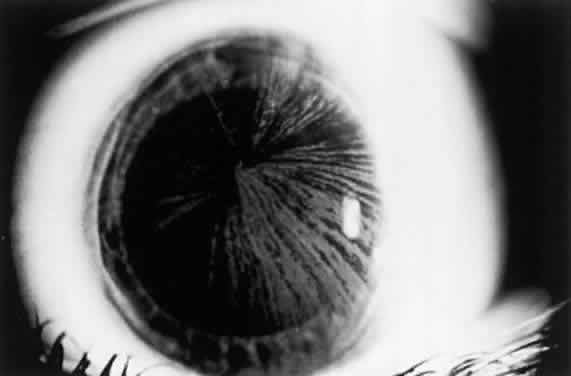

OCULAR FINDINGS. One of the few truly diagnostic and pathognomonic physical signs in clinical medicine is a Kayser-Fleischer corneal pigment ring found in patients with Wilson's disease (Fig. 5).This ring is recognized as a golden-brown, ruby-red, or green band of 1.0 to 3.0 mm, starting at the limbus but at the level of Descemet's membrane.53 The color of the ring is presumably caused by scattering and reflection of incident light and by photointerference effects created by the layers of copper granules. Such variables as size, shape, and unit density of the granules may account for the different appearances of the Kayser-Fleischer ring. The course of the Kayser-Fleischer ring has been well documented.54,55 The site of earliest pigment deposition is an arc in the superior periphery of the cornea from the 10- to 2-o'clock meridian. The arc spreads slowly toward the horizontal plane and gradually broadens. Later in the progression of the ring formation, a band appears inferiorly as a crescent stretching from the 5- to 7-o'clock positions. In time, the two arcs meet. With treatment, the sequence of events is reversed, and after the copper has reabsorbed, a pitted or beaten silver pattern may become apparent at the previous site of the ring. This is an indication that treatment has produced a negative copper balance.49 Decreased visual acuity is not a problem. Rarely, copper is deposited in the crystalline lens, giving an anterior subcapsular “sunflower” cataract.